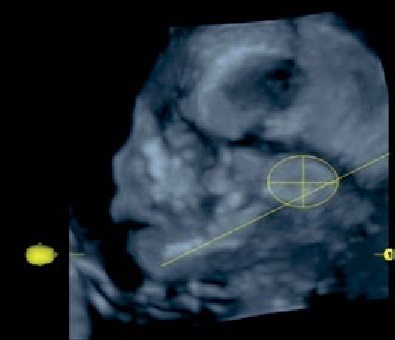

Возрастной период | Схема изменений топографических взаимоотношений ушной раковины плодов относительно нижней челюсти | Ультразвуковая сканограмма головы плода |

24–27 недель | Возраст 26 недель, пол женский |

Примечание. 1 – наружный затылочный выступ; 2 – гнатион; 3 – ушная раковина.

К концу промежуточного плодного периода ушная раковина смещается до уровня отростков нижней челюсти выше вырезки. Ее центральная часть находится выше линии АВ, перпендикуляр от точки С до линии АВ равен 6,1±1,4 мм (таблица 1).

Методом ультразвукового сканирования можно изучить топографию, форму, структуры ушной раковины плода [13]. В исследовании использовались два режима: поверхностной реконструкции и костный (рисунок 1). Во всех случаях определяется условный центр ушной раковины. В костном режиме отчетливо визуализируются костные структуры, в режиме поверхностной реконструкции можно оценить форму ушной раковины и детали строения: завиток, противозавиток, козелок, противокозелок, мочку уха. Форма ушной раковины у плодов вариабельна (таблица 1).

Примечание. 1 – центральная часть ушной раковины; 2 – гнатион.

Рисунок 1. Ультразвуковая сканограмма головы плода. Возраст 20 недель, пол мужской. А – режим поверхностной реконструкции; Б – режим скелетный.

Figure 1. An ultrasound scan of the fetal head. 20 weeks old, male. A – a surface reconstruction mode; B – a skeletal mode.